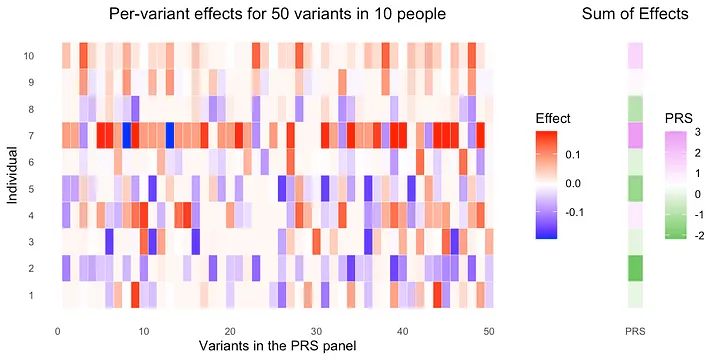

What is a polygenic risk score?

Allelica builds software that enables clinical genetics labs and health systems to deploy robust and accurate Polygenic Risk Scores (PRS), at scale. But what is a PRS?